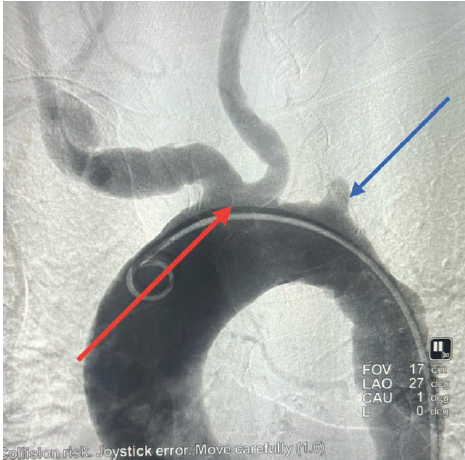

The right radial artery pulse was weak and thready. Surprisingly, the patient’s left radial artery pulse was stronger than the right. The patient underwent cardiac catheterization from the left distal radial artery with the use of ultrasound guidance. Wires were not able to pass into the ascending aorta and an angiogram was taken in turn. The angiogram revealed a 100% occluded left subclavian artery (Figure 1). Femoral access was obtained for selective coronary angiography.